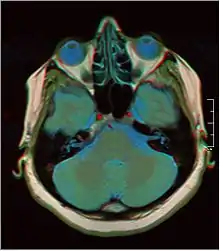

![]() Cross-sectional T1-weighted MRI of a healthy human brain acquired with an ultra high-field MR of 7 Tesla field strength | |

Magnetic resonance imaging of the brain uses magnetic resonance imaging (MRI) to produce high quality two-dimensional or three-dimensional images of the brain and brainstem as well as the cerebellum without the use of ionizing radiation (X-rays) or radioactive tracers.